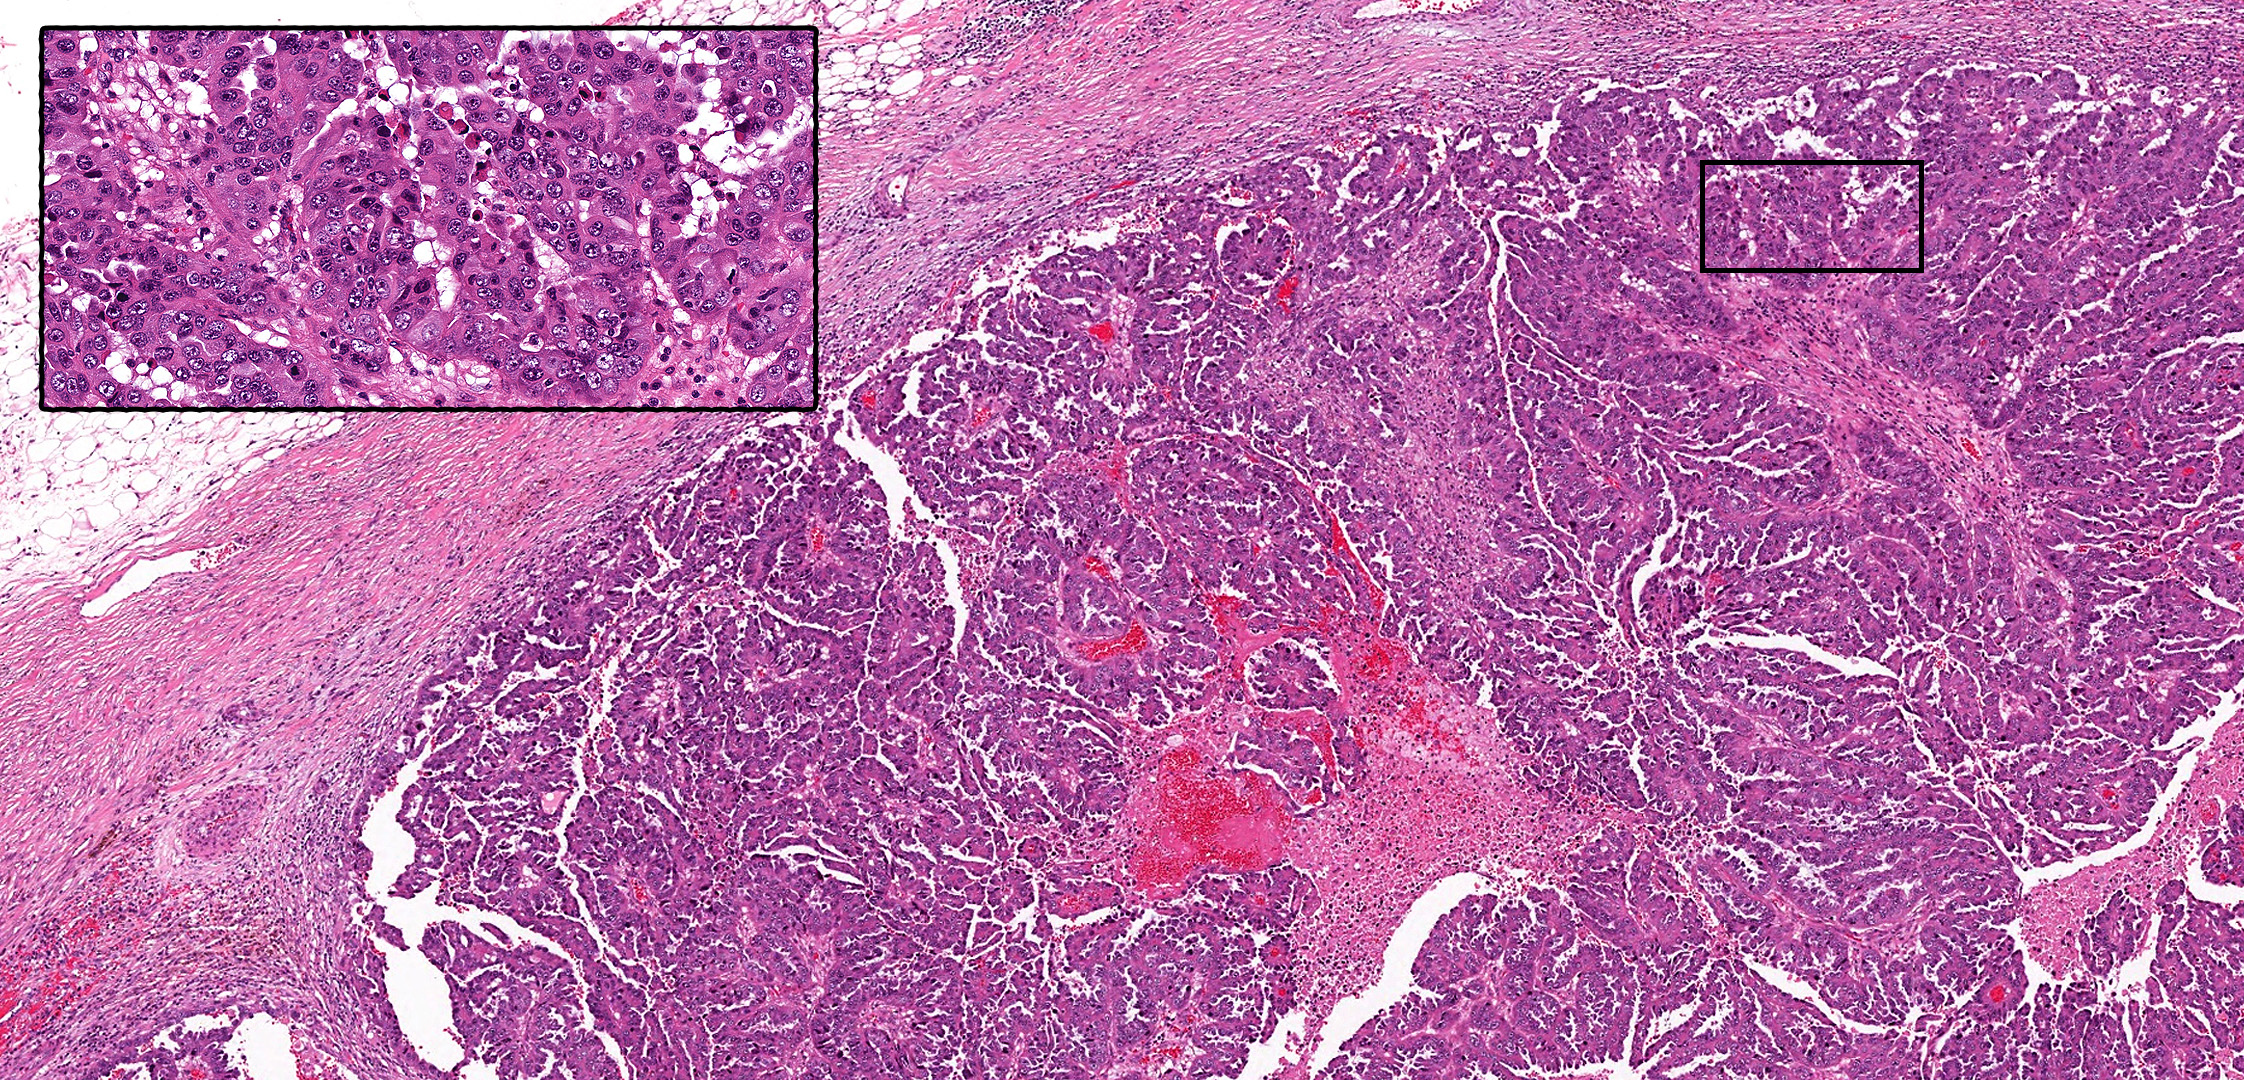

最近有报道描述了伴实性乳头状生长的浸润性小叶癌,与前述实性乳头状癌非常相似。最初报道的三例病变中,作者指出其具有明显的实性乳头状结构(即肿瘤细胞形成实性巢状,伴散在分布的纤细纤维血管轴心),且不表达E-cadherin及β-catenin。下图即为一例实性乳头状浸润性小叶癌的实例:界清的乳头状肿瘤,不表达神经内分泌标记、cadherin-catenin复合体,周边也无肌上皮标记的表达。

图9.类似实性乳头状癌的浸润性小叶癌。本例表现为上皮细胞构成的实性、界清肿物,其间散在纤细纤维血管轴心;与实性乳头状癌存在显著相似性。免疫组化ADH5多重染色(包括染成红色的CK7、CK18以及染色棕色的CK5、CK14、p63)证实并无肌上皮;且肿瘤细胞不表达Syn、E-cadherin。